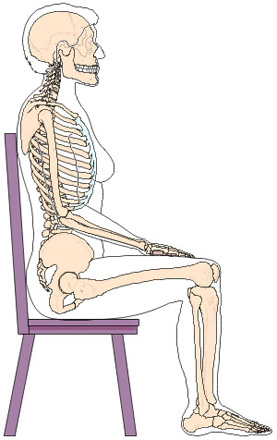

5. Bei der Abbildung kann man ersehen, dass wir auf den Beckenhöcker sitzen. Wären es die sogenannten Beinlängen-Unterschiede, müssten die Beckenkämme über die statische Mittellinie vermessen, ausgeglichen sein. Leider ist dies nicht der Fall. Mit unserem Pat. Statik-Mess-system können wir dies in unserem Schauraum über die Statik-Vermessung aufzeigen. |

Beim Menschen werden Fussbelastungsplatten für Einlagen mit Computer aufgenommen.

Wie werden dabei die Fehlbelastungen ausgehend vom Beckentiefstand, der seitlichen Hüftverschiebung, der Oberkörper-Ausweichhaltung, die zu veränderten Bein- Fuss-Stellung führen, berücksichtigt?

Befindet sich das Becken nicht Waagrecht und Senkrecht im Lot, werden diese Fehlkräfte mit den Ausweichhaltungen auch in der Bewegung bemerkbar machen.

Laufbandanalysen: Welche Ursachen bezogene Aussage können diese über eine schiefe Beckenebene geben?

Was kann eine solche Aufnahme ohne Muskelspannung aufzeigen? Über die Knieentlastung verändern sich Hüftgelenk- und Rückgrat-Stellungen. Wie kann somit eine Stellungsveränderung z.B. über eine einseitige Knieblockade, oder eine Stellungsveränderung der Beinschenkelwinkel zum Becken, eine schiefe Beckenebene festgestellt werden, die eventuell Gelenk oder Rückenbeschwerden verursachen können. Weiter verändert sich die Rückgrat-Stellung. Wie werden dabei Hohl- und Flachrücken im Zusammenhang beurteilt? |

Knie-Unterlage zur Entlastung Ein Körper ohne Belastung stellt wohl ein optisch genaues Bild dar, kann jedoch keine Auskunft über einen fehlbelasteten Körper geben. Dabei fehlen auch folgende Fragen: Haben Sie Angst, Angstinformation erhalten Alle diese |